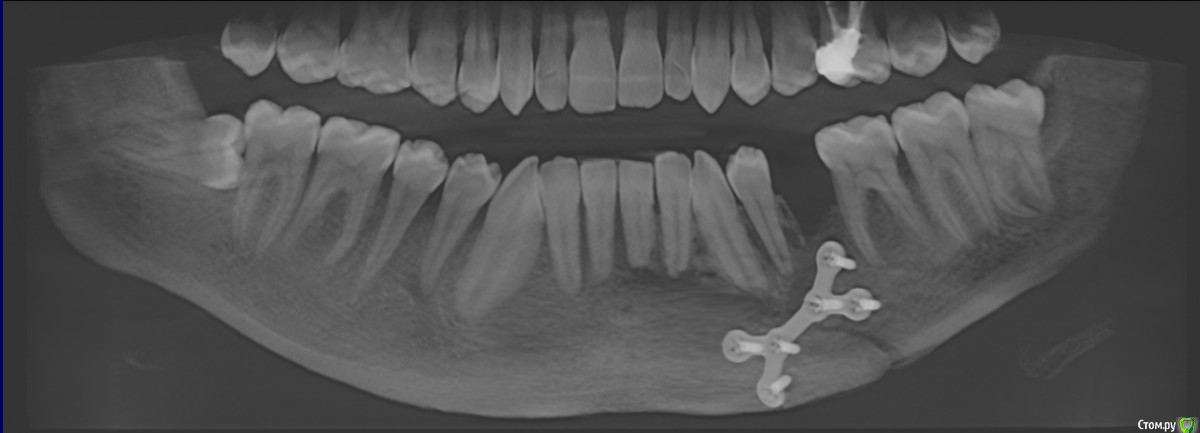

senchauser001 Опубликовано 17 октября, 2015 Поделиться Опубликовано 17 октября, 2015 Здравствуйте, уважаемые доктора. 2-го августа я получил одеосторонний перелом нижней челюсти со смещением, также был отломан альвеолярный отросток с 1-го по 5-ый зубы. Травма была очень серьезная. 3-го числа сделали операцию - остеосинтез титановой пластиной, наложилы шины, челюсти тягами не смыкали. Хирург попытался сохранить зубы и зафиксировал отломок одним шурупом плстины и шиной. Операцию делали из ротовой полости. Наружних повреждений в рузультате травмы я не получил.Через две недели сняли швы и только тогда я смог достаточно открыть рот чтобы разглядеть все полностью. В области 5го и 4го зубов наружней десны небыло, была видна кость и ушко титановой пластины. Врач удивился, сказал что пока на мне будут шины ничего не возможно сделать, а потом сделают небольшую пластику и все исправят. Назначил пасту солкосерил для регенерации тканей, мол поможет затянуться. Через 3 недели после операции сделали снимок и надели тяги для исправления прикуса. Картина на снимке врачю понравилась. 2 сентября сделали снимок и сняли тяги. Шины снимать не стали, т.к. зубы были подвижны, зашивать дисну также не стали. Велели продолжать мазать мазь, мол пусть сама затянется. 18-го сентября врачь решил зашить дисну, т.к. сама она не затагивалась. Через три дня рана раскрылась. Врач сказал что так не должно было быть, сказал придти через неделю, а пока продолжать мазать солкосерил. Через неделю, когда я пошел к врачю, тот сказал что в результате травмы нарушилось кровоснабжение и зашивать нет смысла, надо подождать. 2 октября наконецто сняли шины. Врачу очень не понравилось состояние зубов, они были подвижны, также он сказал что кость начала рассасываться. С наружней стороны дисна практически опустилась, видны были перегородки, кости еще больше оголились. Врачь направил меня к стоматологу, чтобы тот оценил какие зубы можно сохранить. Стоматологу состояние зубов не понравилась, сказал, что начался некроз кости и для адекватной оценки нужно сделать 3d томографию челюсти. Когда стоматолог рассмотрел томоргафию, то пришел в ужас и сказал что возможно придется удалять все 4 зуба, а также поврежденную кость. Я обратился в другую больницу на консультацию к члх, который осмотрев меня, и посмотрев томографию однозначно сказал, что нужно удалять весь отломок и отправил обратно к моему врачю. Я опять пошел к своему члх с этой томографией и только тогда, когда он ее посмотрел, то его осенило. Он сказал что отломанный альвеолярный отросток лишен кровоснабжения, он секвестируется, начелся некроз кости и его нужно удалять. Если бы не эта томография, он собирался удалить 2-ой и 4-ый зуб и натянуть все дисной. Все это время у меня не было не повышенной температуры, не болевых ощушений, ничего, что указывало бы на наличие восполительного процесса или чегото еще. В результате я потерял более чем 2 месяца безрезультатно. Сам члх достаточно опытный врачь, начальник отделения и кроме него меня смотрели другие члх из той же больницы. Если бы стоматолог не направил бы меня на 3d томаграфию, то не известно что было бы дальше. Теперь я не знаю как я могу доверять этому врачю, если он вовремя не обатил на это внимание и вел меня совсем другим путем? Каким образом после операции была оголена такая большая чась кости? Возможно ли было сохранить хотябы альвеолярный отросток удалением зубов? Как теперь можно будеть вставлять импланты? Стоит ли менять врача? Ваще мнение для меня очень важно. Заранее Спасибо! 1 Ссылка на комментарий

senchauser001 Опубликовано 20 октября, 2015 Автор Поделиться Опубликовано 20 октября, 2015 Сегодня сделалаи секвестрэктомию, удалили весь секвестр. Скажите пожалуста, нужно ли снимать имплант (пластину) и через скодько времени? Ссылка на комментарий